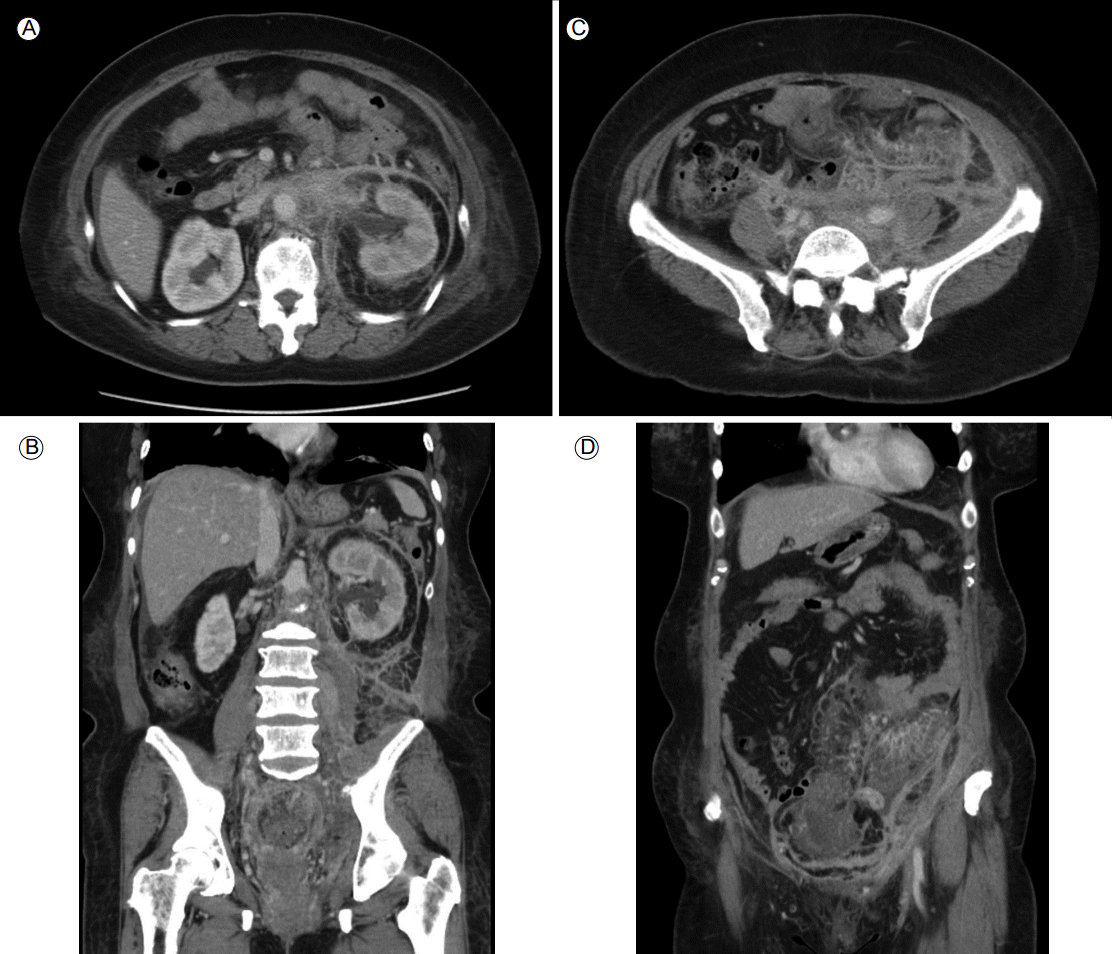

Figure 2.

Abdominal computed tomography showed diffuse infiltrating soft tissue lesions in the retroperitoneal space (A, B) and in the extraperitoneal space around the urinary bladder and the perirectal space (C, D).